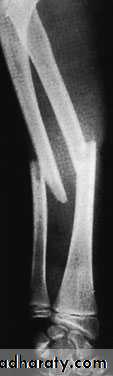

X-ray

With isolated fractures of the ulna, it is essential to obtain a true anteroposterior and true lateral view of the elbow. In the usual case, the head of the radius (which normally points directly to the capitulum) is dislocated forwards, and there is a fracture of the upper third of the ulna with forward bowing.